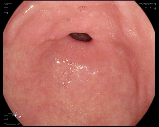

4.1.7 Gastrointestinal endoscopy

Endoscopies are used to detect diseases in the human digestive system. Images from inside the gastrointestinal tract can help physicians detect diseases early. The used dataset 777https://www.kaggle.com/datasets/abdallahwagih/kvasir-dataset-for-classification-and-segmentation contains eight image categories of the digestive system obtained through the endoscopy imaging technique, as shown in Fig. 8. There are a total of images that can be used in training and testing ML algorithms.